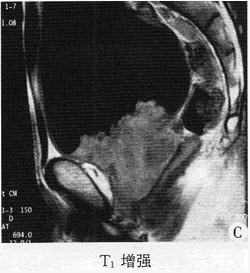

43������ѡ���� �����У�44�ꡣ���ϸ���ʹ���꣬���ذ��ϸ�������1���£��鸹�͡��ɲ���ģ���Ż�¡���к����С�������������½�5kg���������Ҹβ�ʷ���ꡣ���壺T36.7�棬P78�Σ��֣�R18�Σ��֣�BP110��70mmHg��ȫ��Ƥ����Ⱦ����Ĥ��Ȼ�Ⱦ����ƽ�������ϸ����������ϸ�ѹʹ�������ţ������״�����5cm����Ե�ۣ����ͣ��д�ʹ��Ƣδ��������ߵ����������ƶ������������Ͻ�ߵ���ڵ����䣬����ߵʹ�����ﳦ����8�Σ��֡�������飺Hb89g��L��WBC5.6��109��L��ALT84U��L��AST78U��L��TBIL30��nol��L��DBIL10��mol��L��ALP188U��L��GGT64U��L��AFP880ng��ml��CEA24mg��ml��B��������Ҷʵ����ռλ�Բ���8cm��������ܲ����š�

������鷢�ָ���ҶԼ3cm�飬AFP�������ߣ���Զ��ת�ƣ��ι��ܻ������������߾ܾ�����������ʵ������ǣ���